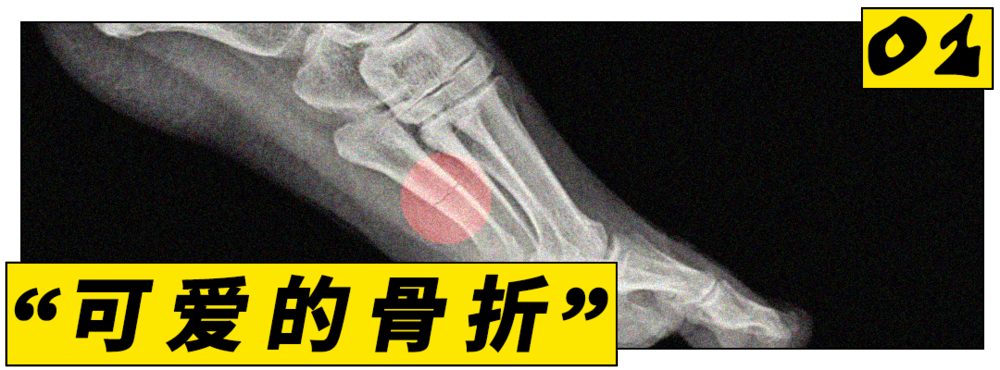

21世纪,跑步的火爆程度早已超出了一项运动本身。要问2026年跑步圈最火的话题是什么,应力性骨折一定榜上有名。

用一句话概括的话,它是由长期运动所引发的微小骨裂,也或许是今年最流行的伤痛。根据Google搜索趋势,今年关于应力性骨折的关注度已创下了自2004年以来的新高。

这可能意味着,我们即将见证人类史上第一个骨折潮流。

骨折不是稀事,但奇怪的点在于,过去会患上应力性骨折的往往是专业的跑步选手。据统计,大约40%的运动员在一辈子里至少会得一次应力性骨折。

一篇学术报告也指出,这种骨折常见于精英运动员和军事训练人群。这些人的下肢会长期承受重复性冲击负荷,一般人几乎没可能不会受这样的伤。

数据显示,一项面向成年女性跑者的在线调查显示,约25.4%的受访跑者有过应力性骨折的历史。